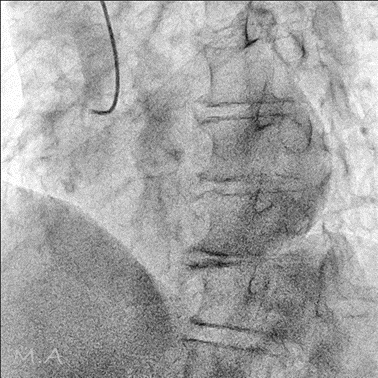

血管撮影装置

当院は令和6年3月の新病院発足に伴い、より高精度で安全な検査・血管内治療(IVR:Interventional Radiology)を提供するため最新の島津製作所製バイプレーンシステムTrinias B12s(Opera smart)を導入しました。

平面型X線検出器(FPD:Flat Panel Detector)を搭載し、カテーテルを用いた高度な血管内治療においてより少ないX線で高い解像度の画像を描出可能となりました。

バイプレーンシステムを採用したことにより、一回の造影剤注入で2方向撮影が可能となり、従来のシングルプレーンと比較して造影剤使用量を半分程度に抑えることができ、被ばくを低減すると共に検査時間の短縮にも繋がり、より患者さまの負担を軽減することが可能となりました。

冠動脈造影検査(CAG:Coronary Angiography)をはじめ、経皮的冠動脈インターベンション(PCI:Percutaneous Coronary Intervention)、下肢動脈のインターベンション(EVT:Endovascular Treatment)、肝動脈化学塞栓術(TACE:Transcatheter Arterial Chemo-Embolization)等、心血管領域、腹部血管領域における高度なカテーテル治療においてその性能を発揮しております。